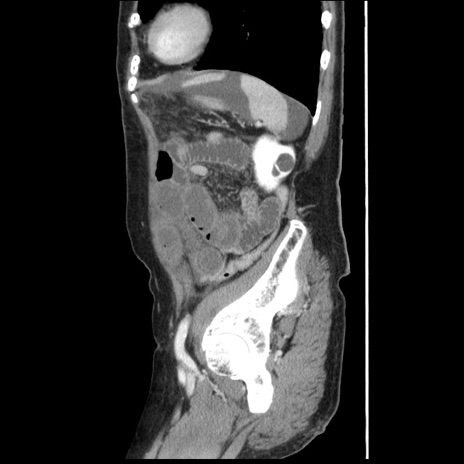

横断像

【症例】80歳代女性

【主訴】腹痛

【現病歴】8時間前から腹痛あり来院。

【既往歴】糖尿病、脂質異常症、子宮体癌にて子宮全摘術

【身体所見】意識清明・会話良好だが腹痛で苦悶様、全腹部にわたって反跳痛と圧痛あり

【データ】WBC 13600、CRP 0.14、LDH 224、CK 90